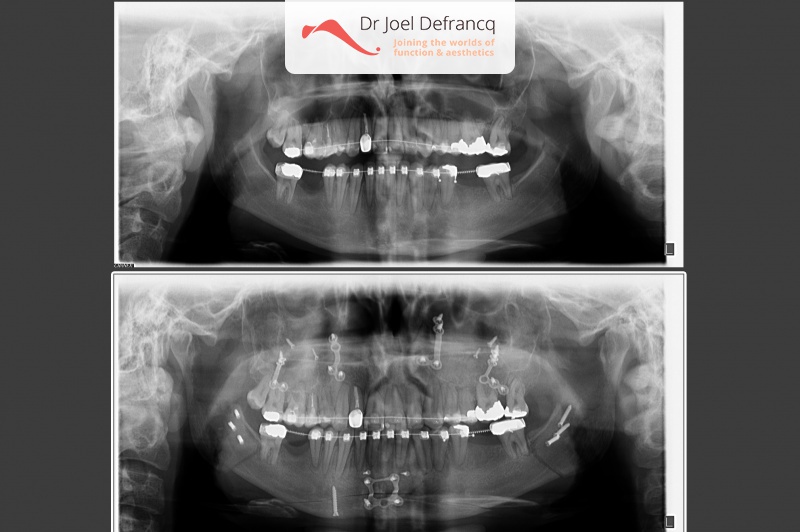

Kaakchirurgie

- Verlenging onderkaak (BSSO)

- Verlenging bovenkaak (Le Fort I)

- Vertikale verlenging bovenkaak (Le Fort I)

- Kinchirurgie